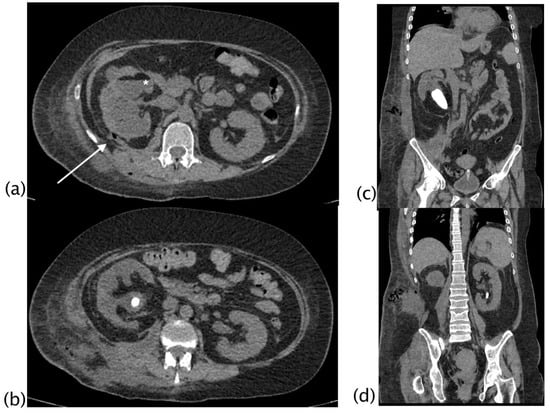

Figure 6.

Xanthogranulomatous pyelonephritis Stage III—pararenal form CT with contrast agent: axial (a,b,e), coronal (c), and sagittal (d) MPR reconstructions with lung window (e,f). Patient admitted for persistent cough and left basal opacity on chest X-ray examination. On CT examination, morpho-structural alteration of the kidney with gross intraparenchymal collections alternating with dilated calyces is present. An upper polar fistulous via (a,b) is well evident (white arrow) that continues into the lung in direct continuity with a bronchus, more evident in sagittal reconstructions. Recognition of the fistulous via on CT was visible in 22.22% of patients.